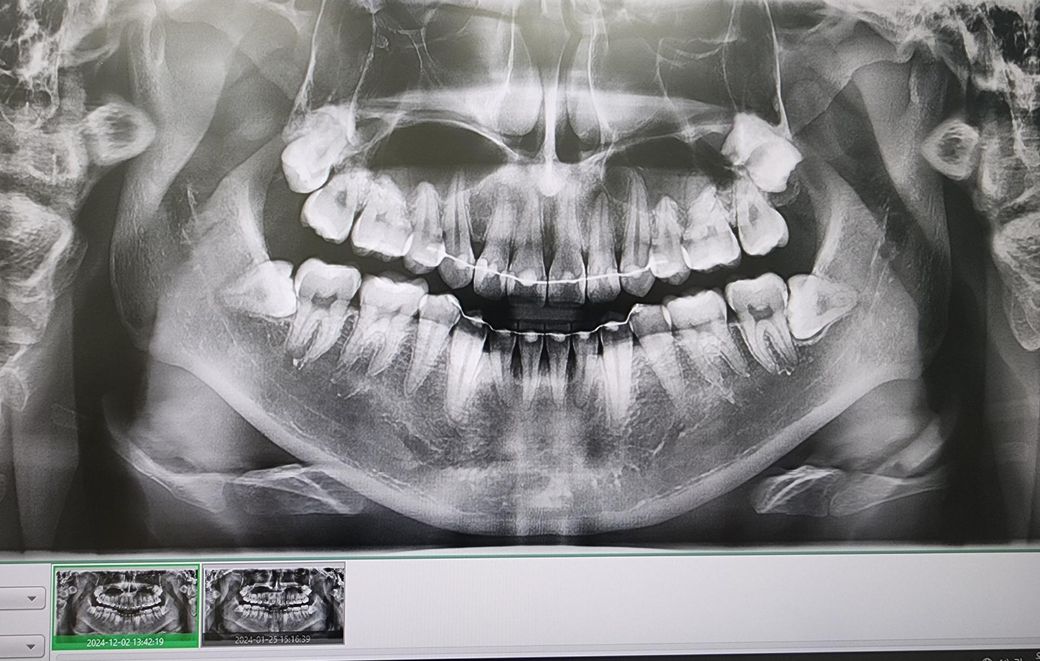

• 3번 째 사진

엑스레이 상으로는 치아 뿌리끝 염증이 더 확장된거 같습니다. 신경치료를 하시는게 좋을것같습니다.

만성농양의 경우 통증은 없기도 합니다 통증과는 별개로 뼈는 염증때문에 계속 녹고 있는거고요 가급적 신경치료 빨리 받으면 좋습니다